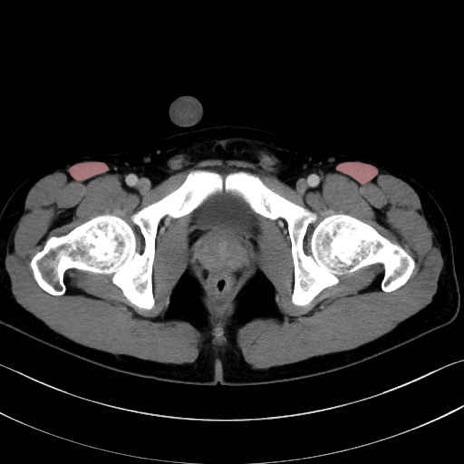

内閉鎖筋 (Obturator internus)

外閉鎖筋 (Obturator externus)

大腿方形筋 (Quadratus femoris)

恥骨筋 (Pectineus)